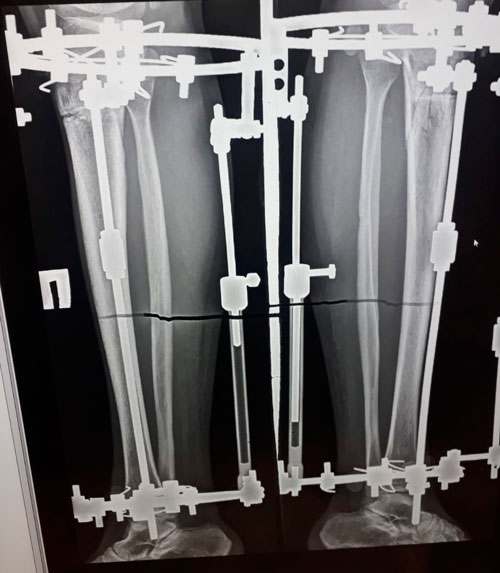

рентген после круток.

рентген в 62 дня.

рентген в 92 дня.

Чере 2 недели ждём на снятие аппаратов!